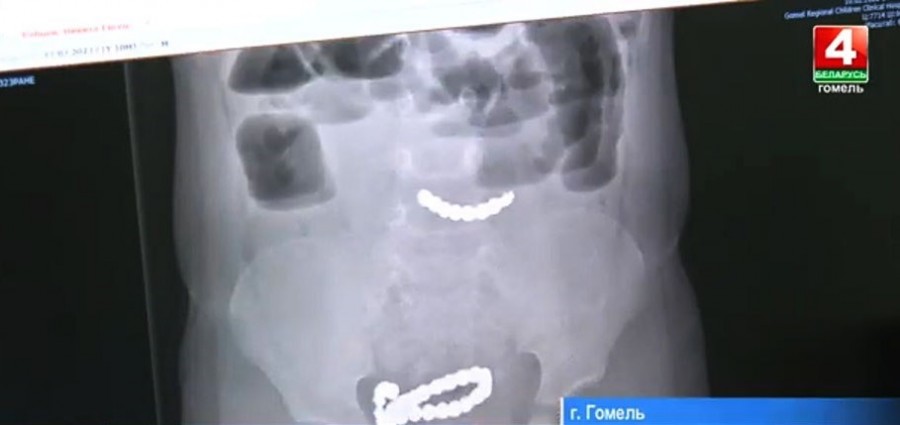

Хирурги Гомельской областной детской клинической больницы провели операцию на кишечнике двухлетнего ребенка, достав оттуда 20 магнитов.

В ходе операции инородные тела извлекли, пришлось удалить три фрагмента кишки, на каждом из которых образовалось по два сквозных отверстия. После этого целостность кишки восстановили. Впереди у мальчика долгая реабилитация. Нужно, чтобы кишечник сросся и заработал.